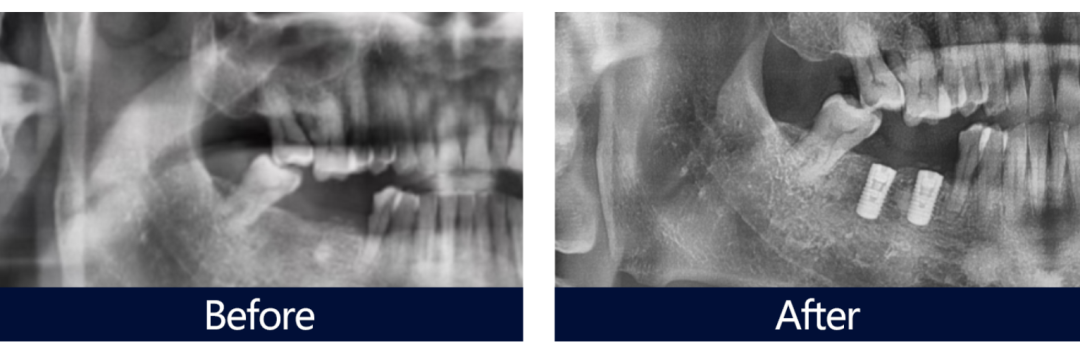

剛出手術室的鮑叔叔臉上麻藥沒過,但神色十分輕松,他高興地說:“一點沒感覺到痛,王醫生技術非常好,沒想到那么快就做完了。”隨后,王鋒醫生現場展示了鮑叔叔術前術后的口腔全景片對比,在高端數字化設備的掃描下,大家可以清楚的看到,憑借3D導板的領航和王鋒醫生的精湛技術,兩枚植體以術前設計的完美角度,精準地植入到鮑叔叔的牙槽骨中。

鮑叔叔種牙前后全景片對比